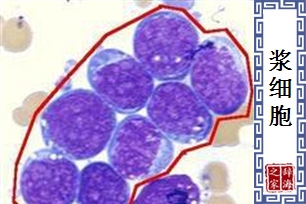

- 由B淋巴细胞转化而来,可分泌和合成抗体的细胞。生成抗体后数天便死亡。

【浆细胞】 图片鉴赏